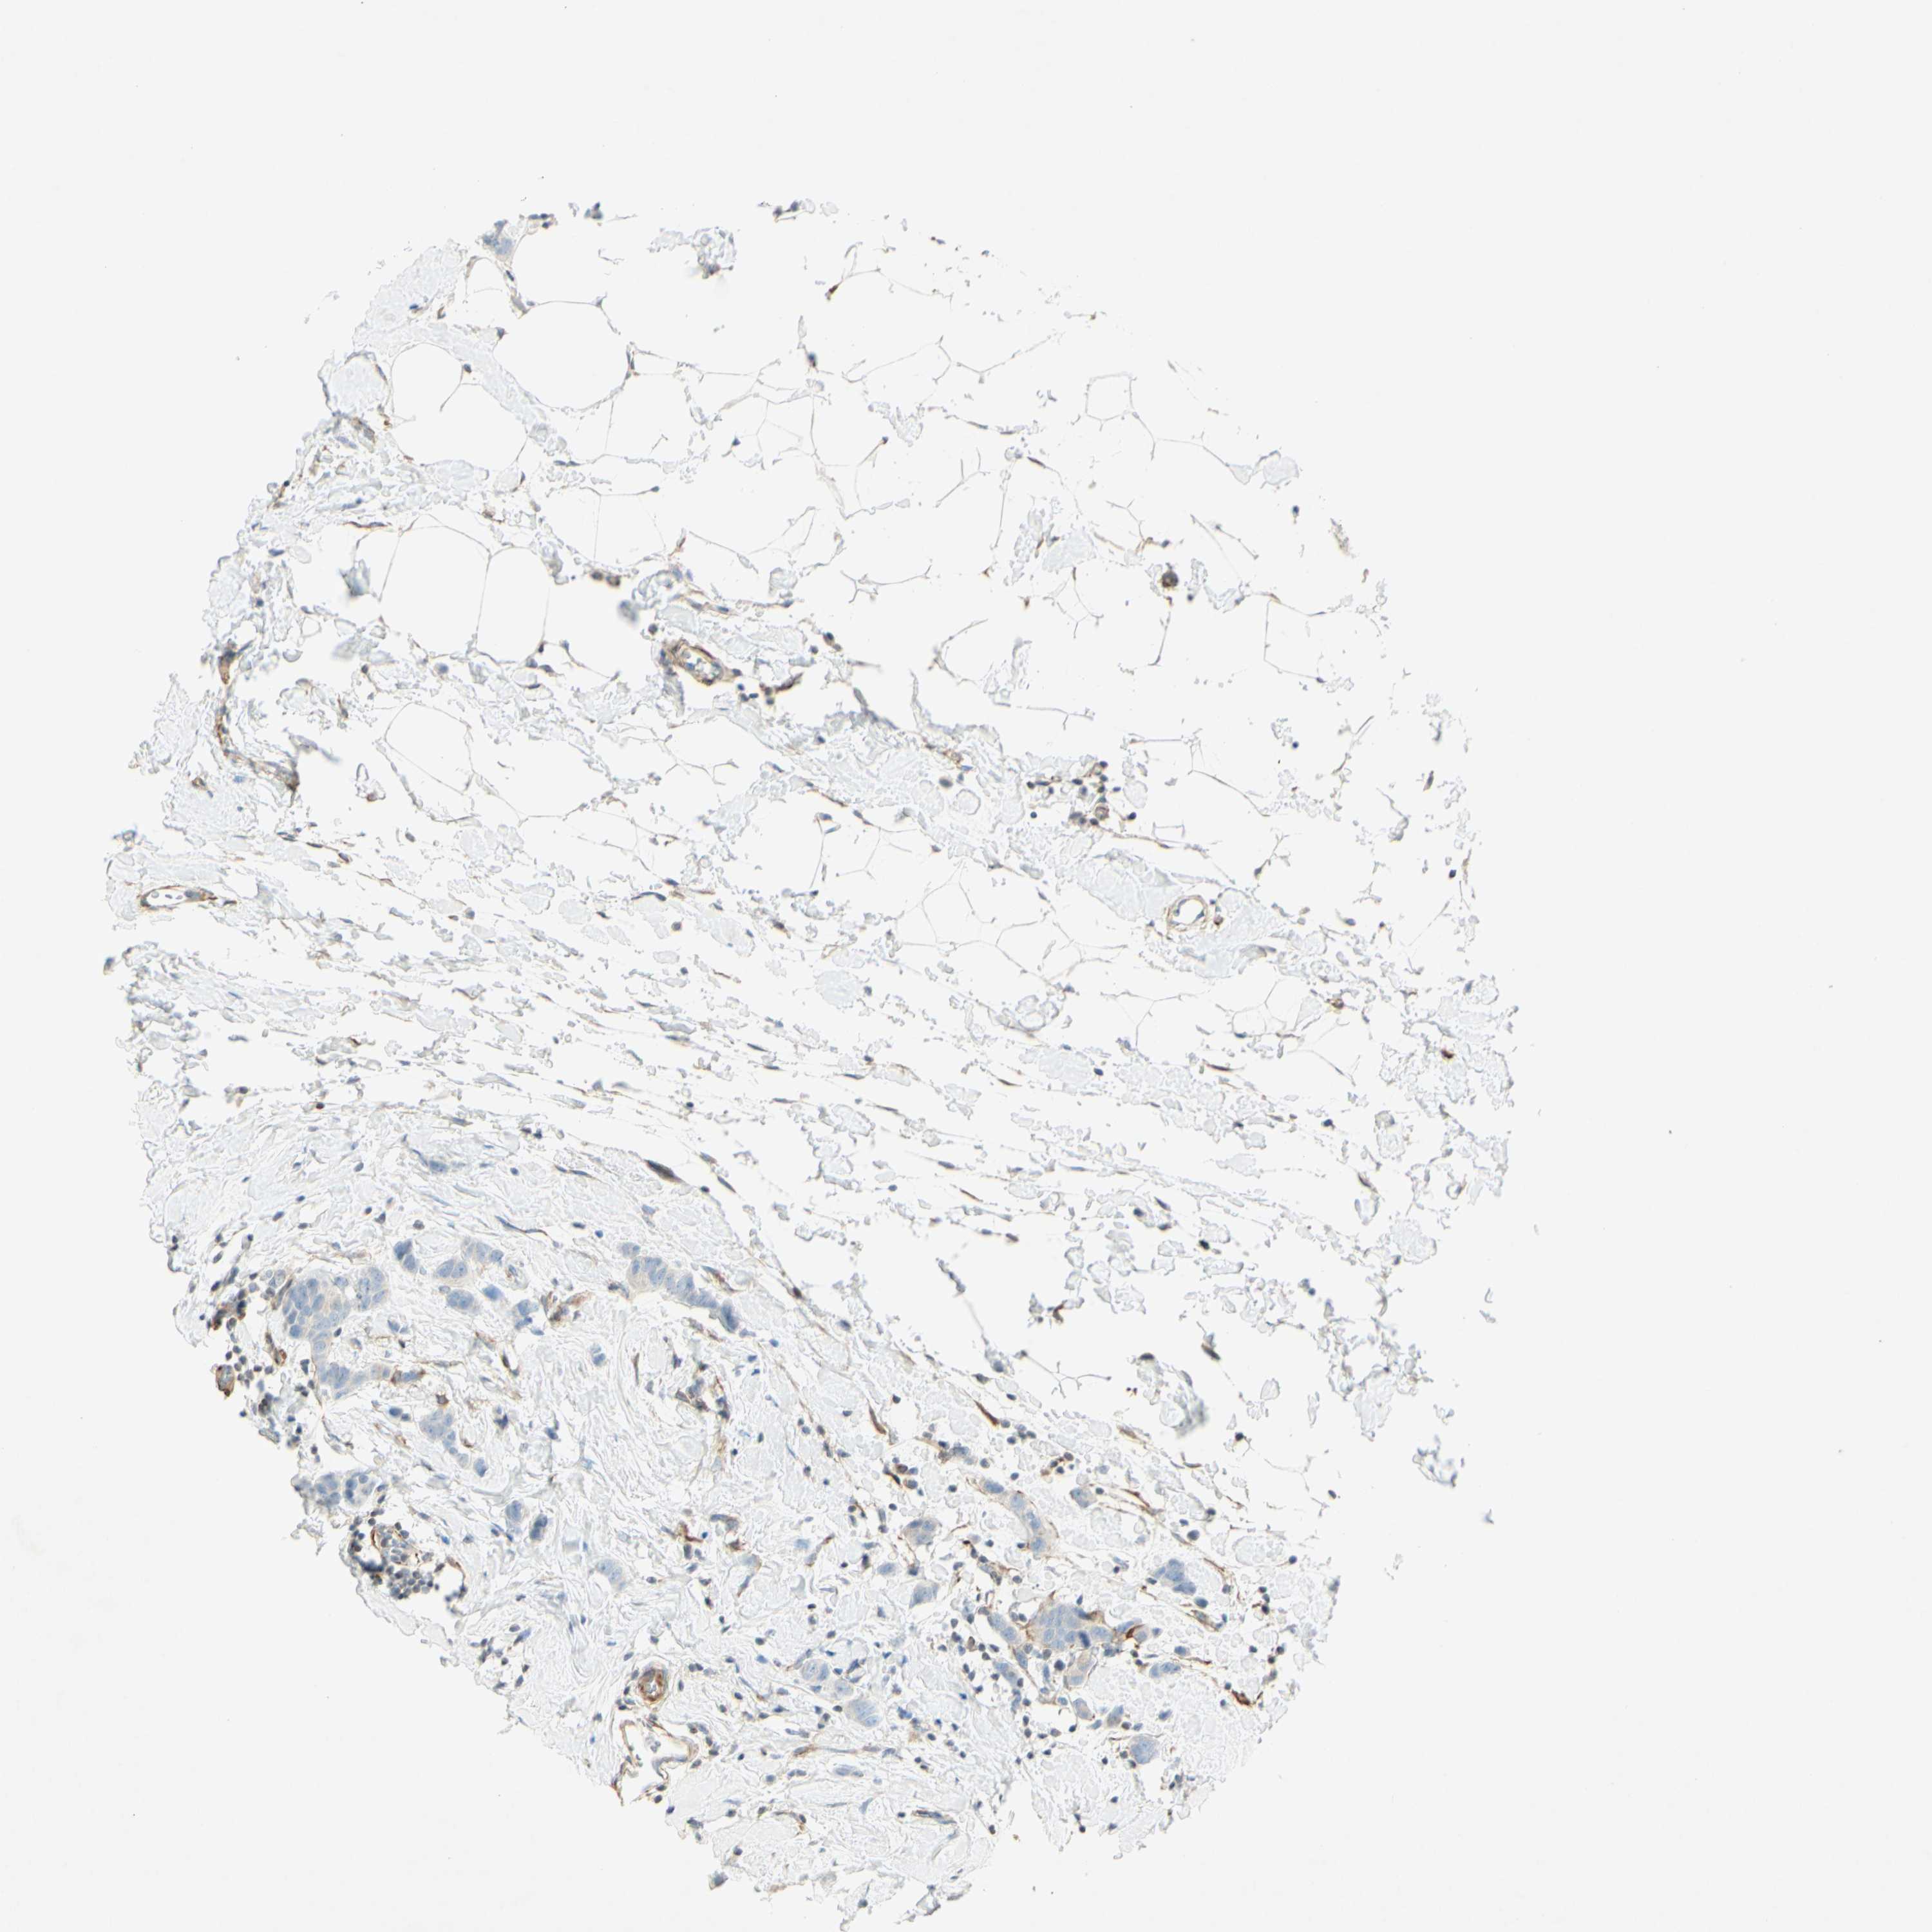

CANCER BREAST CANCER Show tissue menu

BRCA TCGA BRCA VALIDATION PROTEIN EXPRESSION

ANTIBODIES

AND

VALIDATION